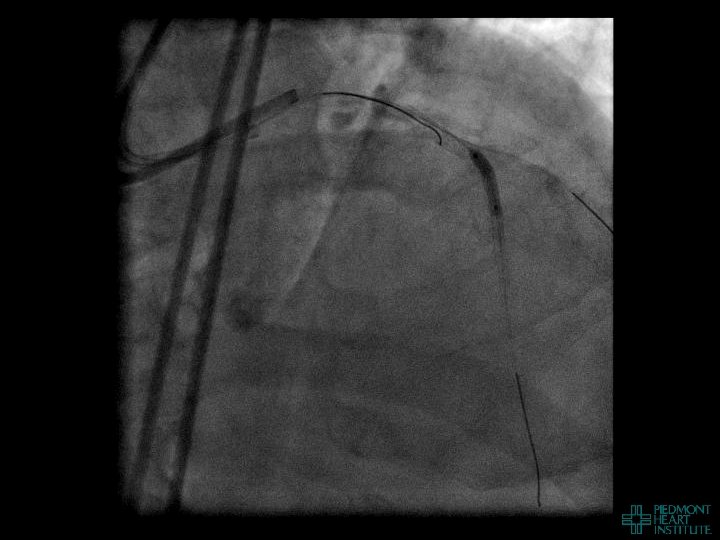

Case Example 2